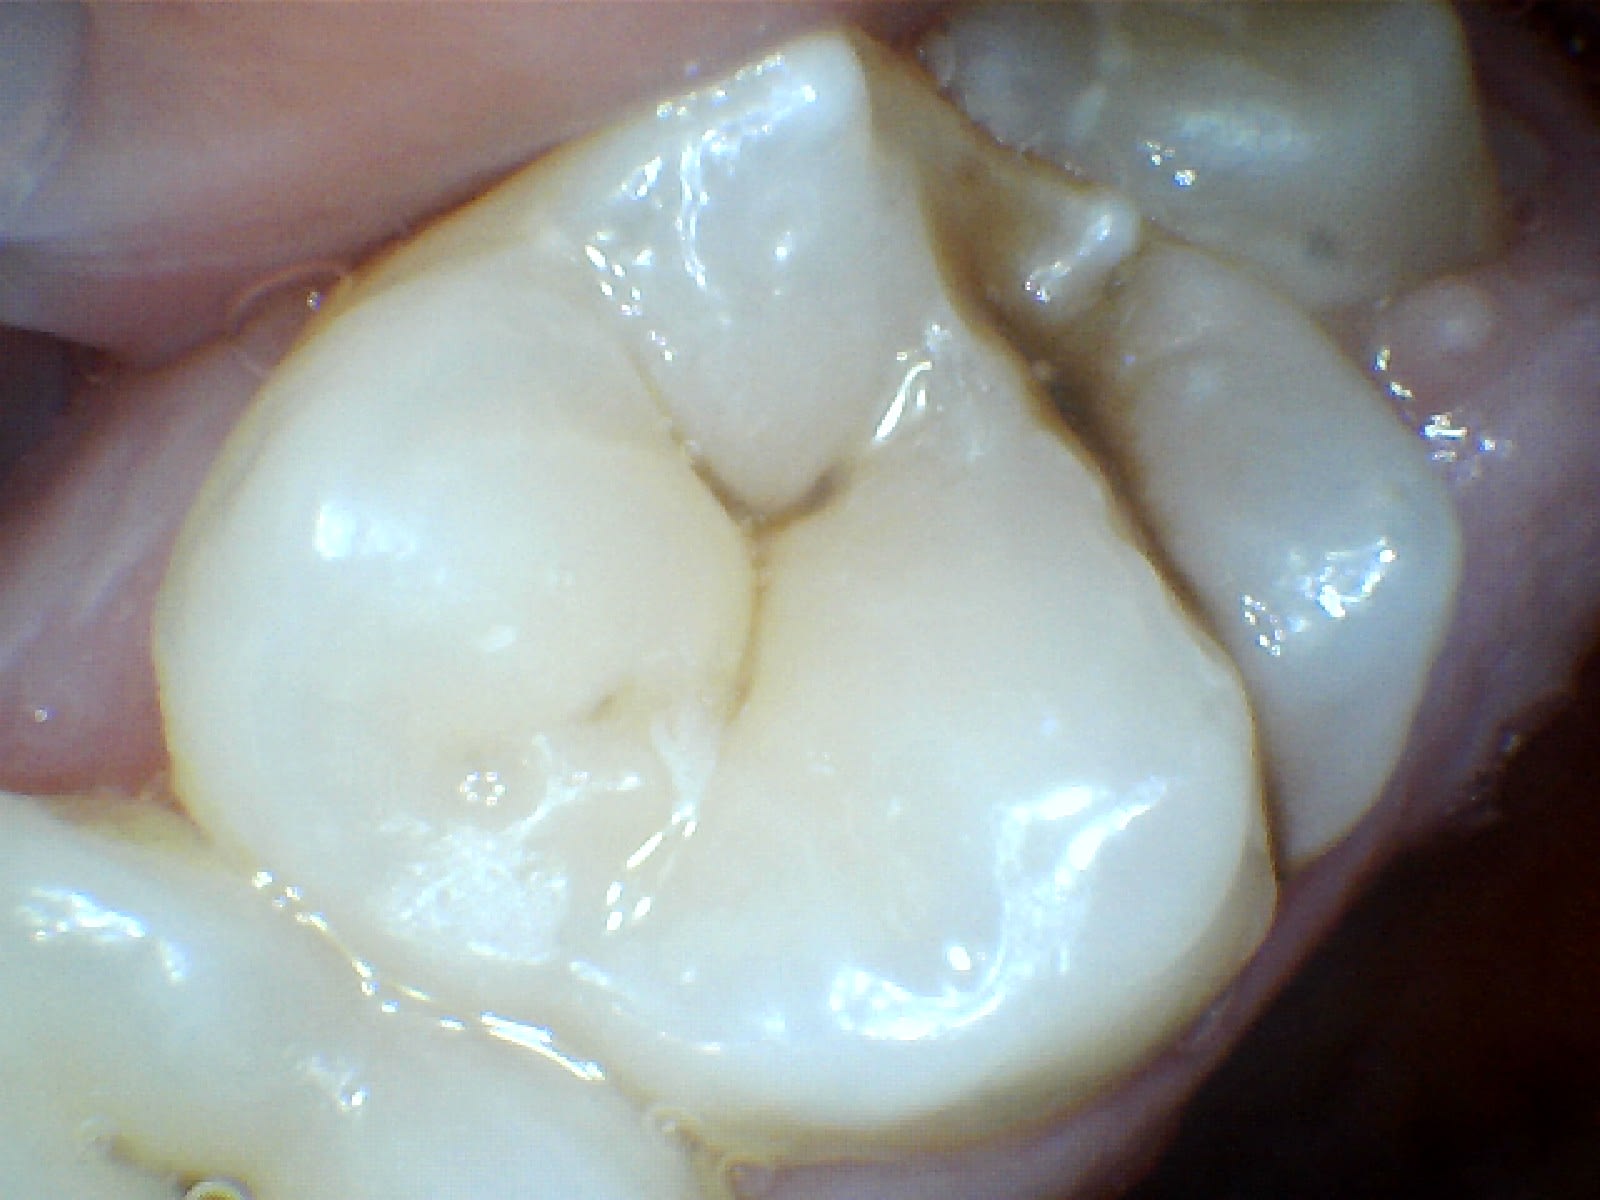

au niveau de la resolution ca donne ca. C'est clair que c'est pas parfait mais je pense qu'on voit ce qu'on veut montrer